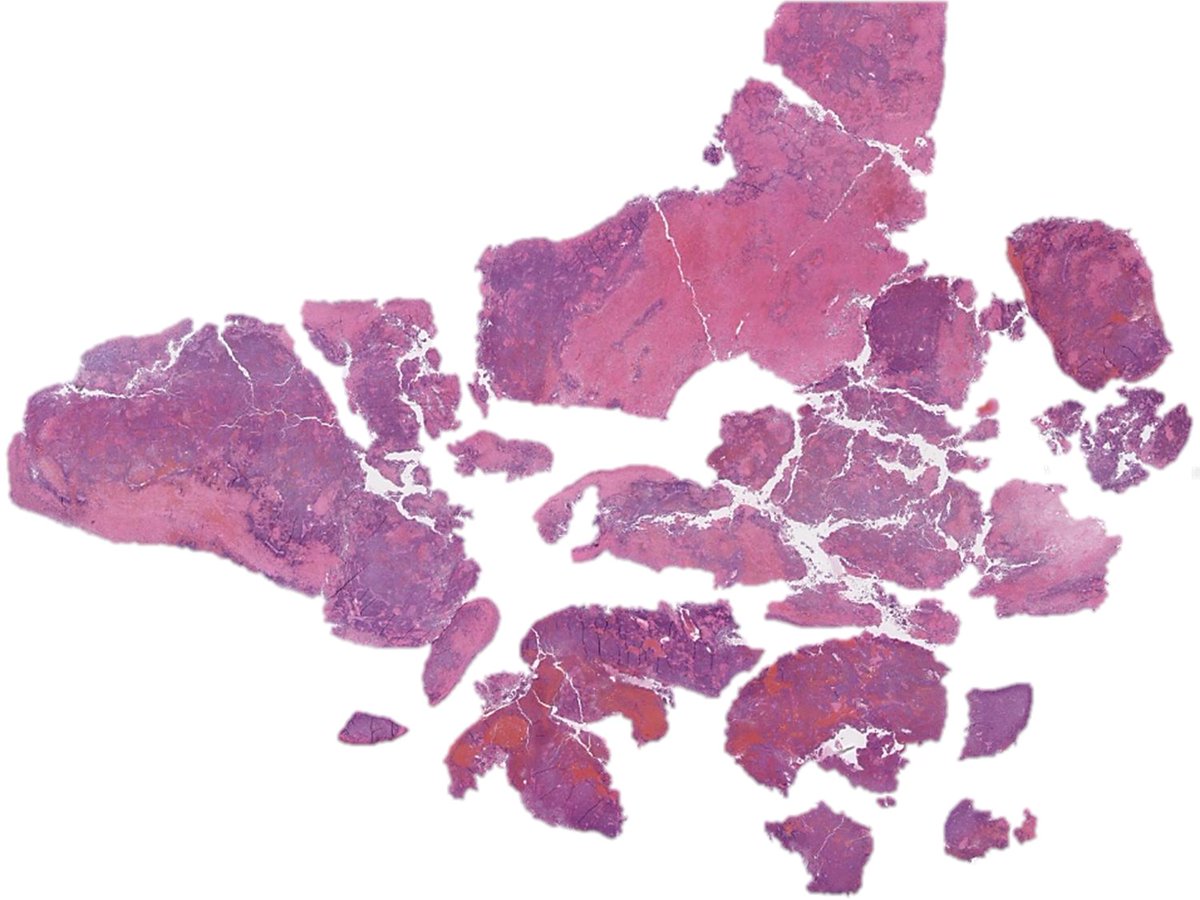

Lung biopsy illustrating a spectrum of involvement by lymphomatoid granulomatosis➡️ 🩸Grade 1: Polymorphous angicentric lymphoid infiltrate without significant atypia; necrosis is absent. Large EBV-positive lymphoid cells are rare. #hemepath #lymsm #thoracicpath #PathTwitter